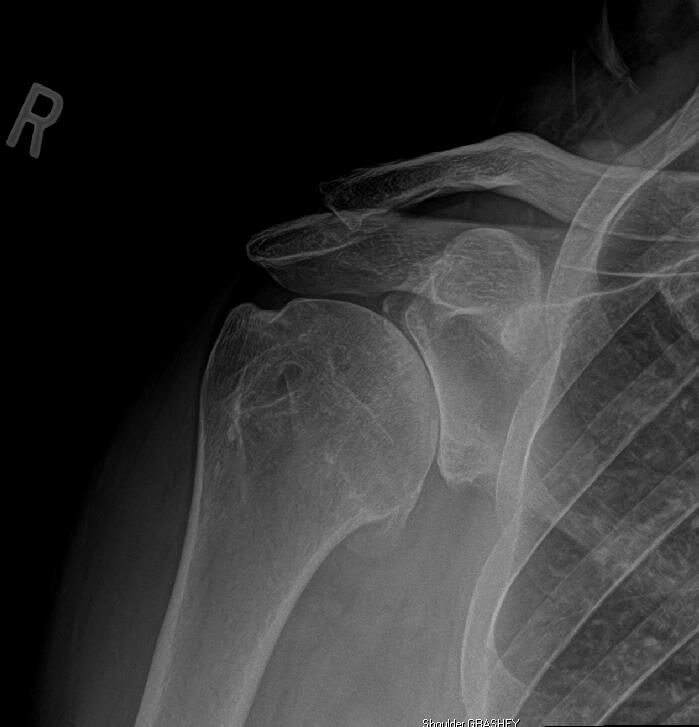

後向脫位(posterior dislocation) 時:

肱骨頭會「卡在盂窩後方」

在 AP view:

- 肱骨頭與盂窩突然沒有「重疊」

看起來像是 盂窩那邊是空的(empty)

稱這種現象為:empty glenoid

正確(B) 盂肱關節後向脫位(posterior dislocation)

沒有重疊了,empty